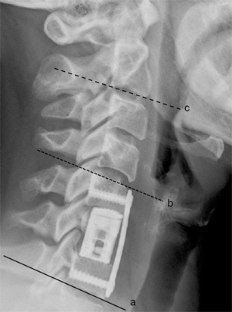

Fig. 2